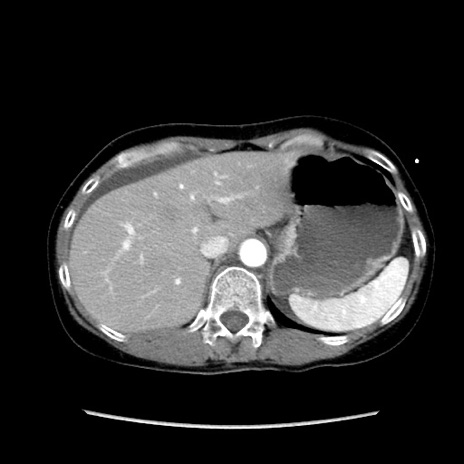

症例32(横断像)

【症例】40歳代 女性

【主訴】上腹部痛、嘔気・嘔吐

【現病歴】約9時間前頃から急に上腹部痛、嘔気、嘔吐が出現。改善しないため救急要請。

【既往歴】子宮頚癌(広汎子宮全摘術、放射線療法)、腸閉塞

【身体所見】腹部:平坦、軟、腸雑音亢進、上腹部を中心に腹部全体に圧痛あり。

【データ】WBC 8400、CRP 0.03